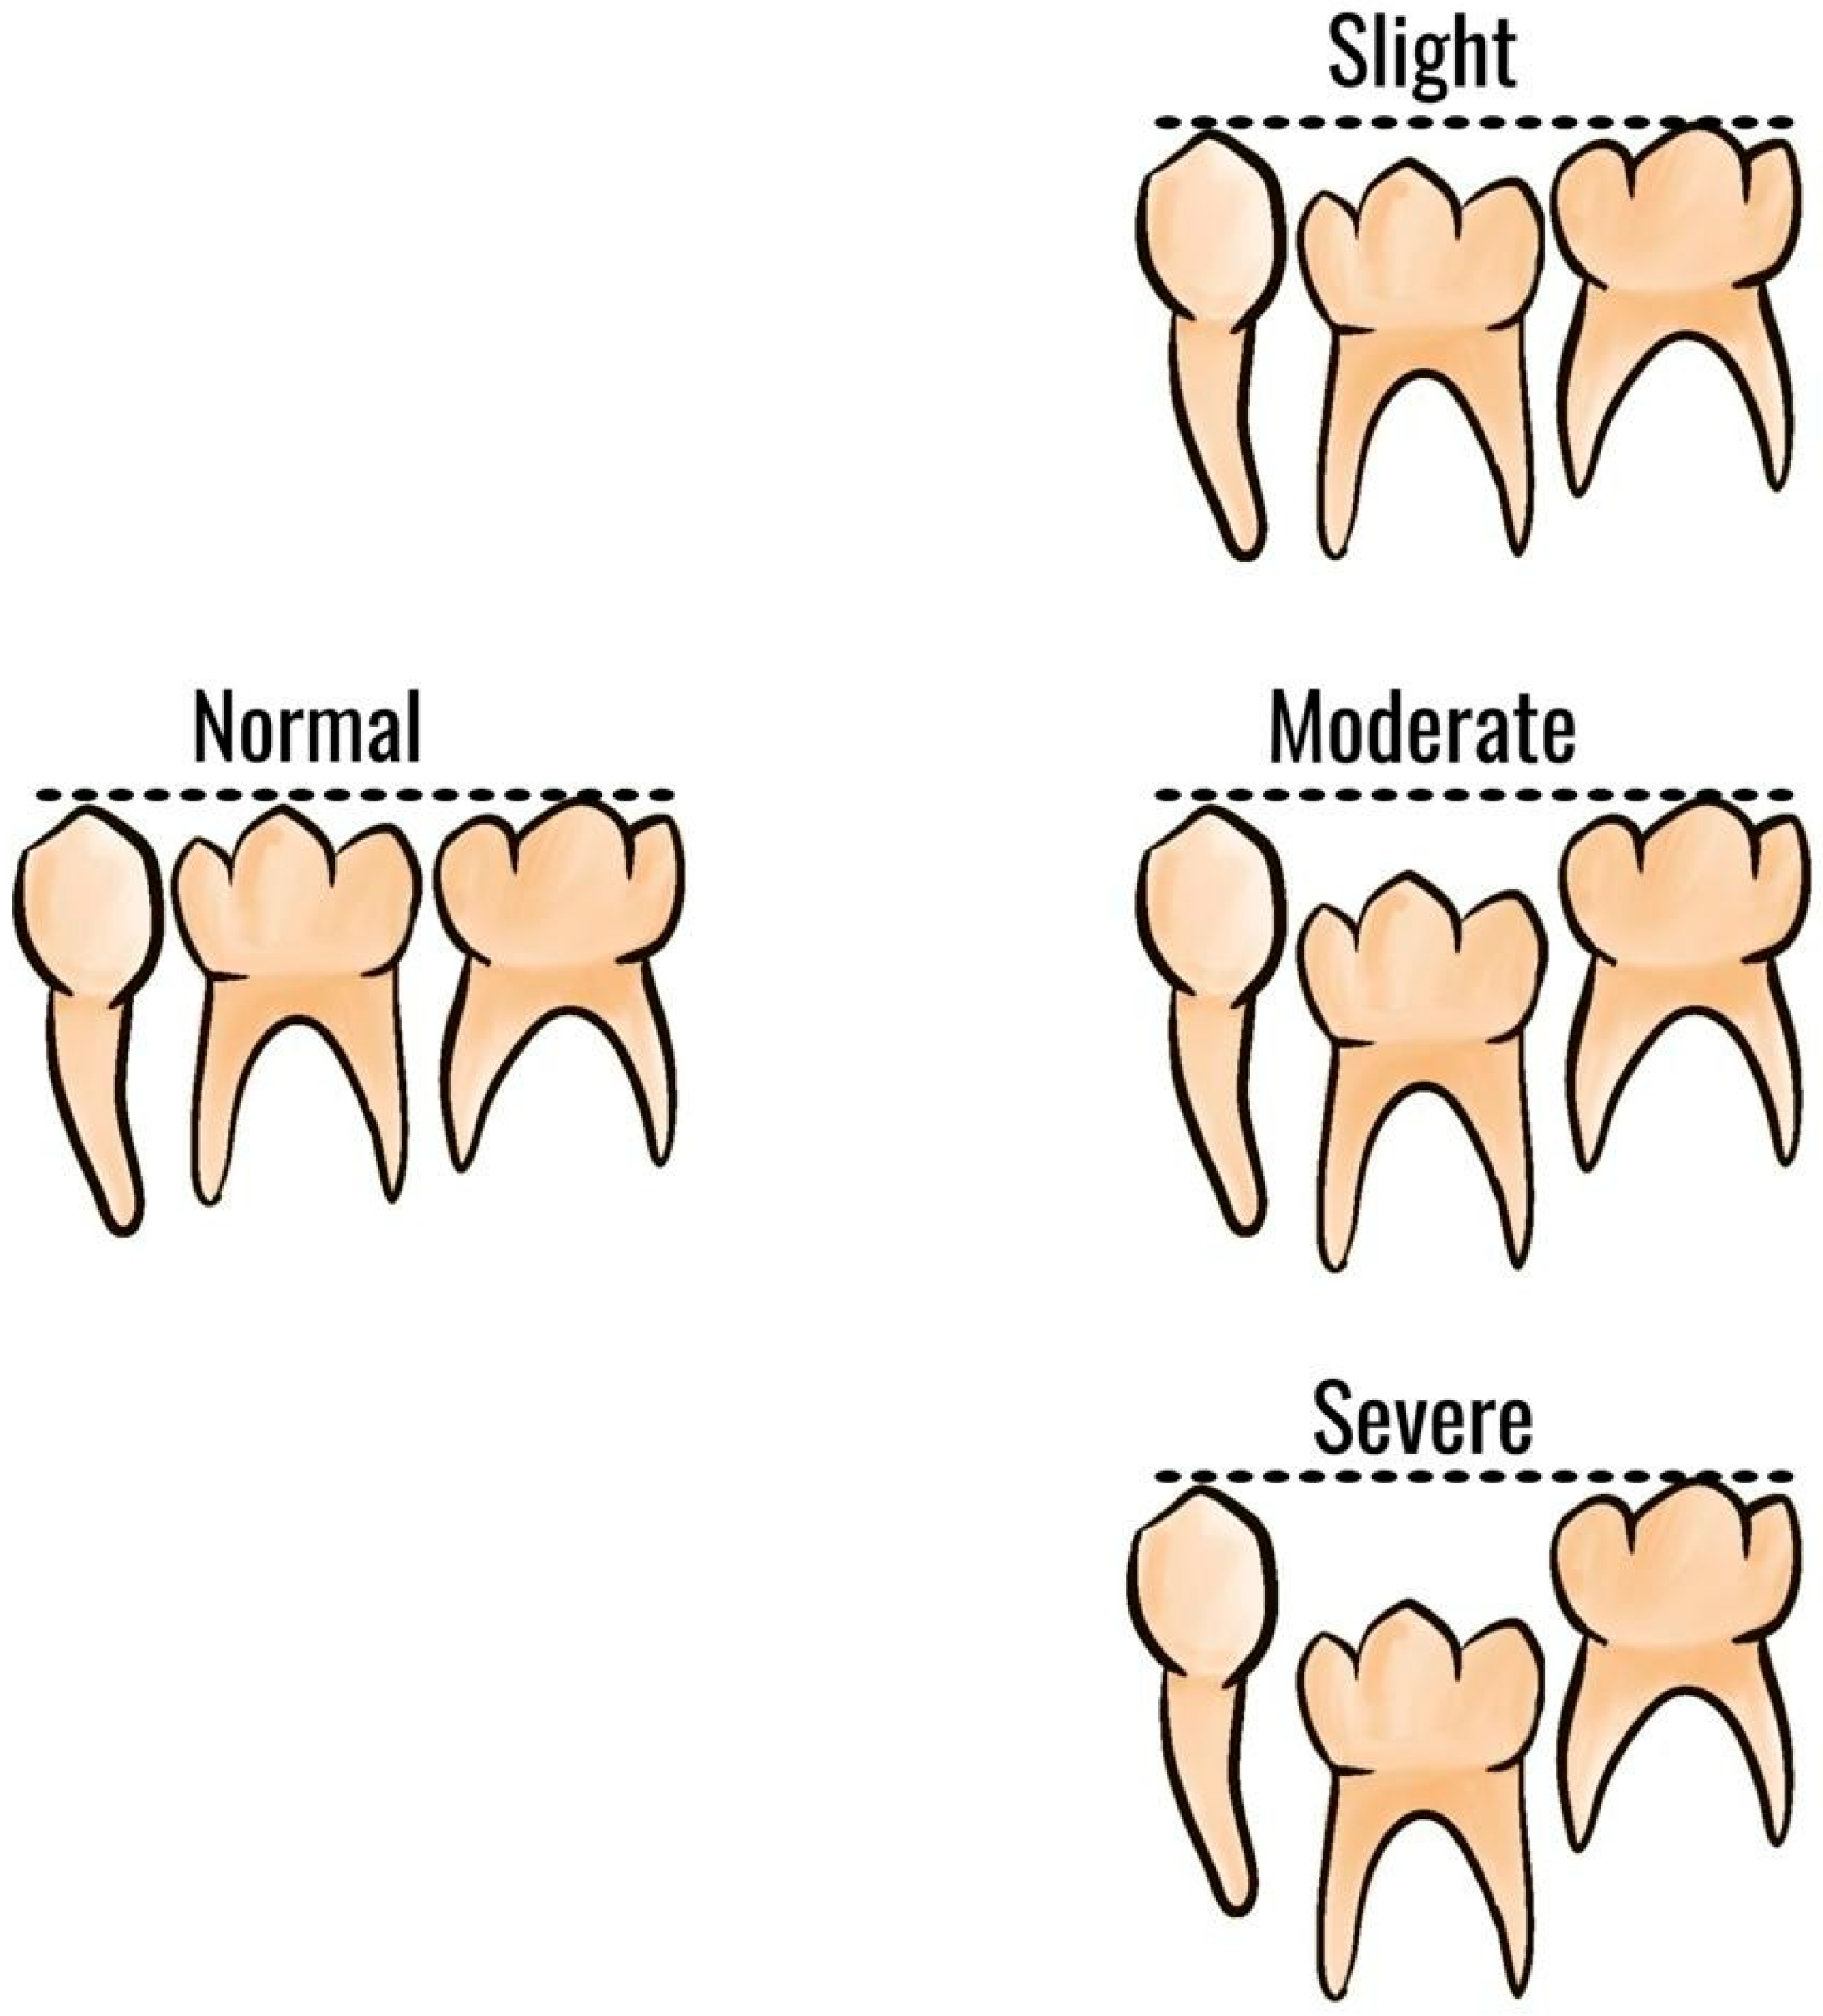

1.2. Clinical Features and Diagnosis

- Eşian, D.; Bica, C.I.; Stoica, O.E.; Dako, T.; Vlasa, A.; Bud, E.S.; Salcudean, D.; Beresescu, L. Prevalence and Manifestations of Dental Ankylosis in Primary Molars Using Panoramic X-Rays: A Cross-Sectional Study. Children 2022, 9, 1188. [Google Scholar] [CrossRef]

- Cardoso Silva, C.; Maroto Edo, M.; Soledad Alvaro Llorente, M.; Barbería Leache, E. Primary Molar Infraocclusion: Frequency, Magnitude, Root Resorption and Premolar Agenesis in a Spanish Sample. Eur. J. Paediatr. Dent. 2014, 15, 258–264. [Google Scholar] [PubMed]